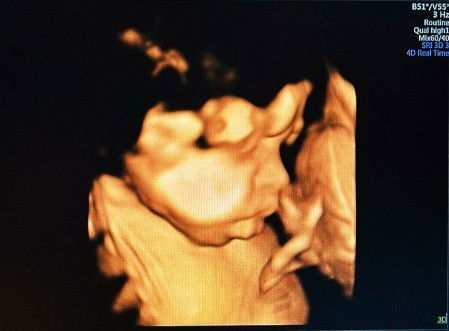

Hasil USG 31week

Masya Allah Tabarakallah, si dedek bibirnya sampe muncis² 😍😍😁 ada yg sama gak bun debaynya bbirnya tebel gitu 😁😁#bantusharing #firstmom #ingintahu #firstbaby